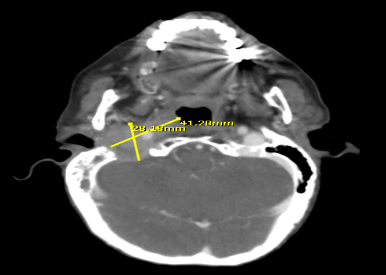

Para julio de 2019 presenta otalgia y otorragia derecha, lo que la lleva a consultar con médico internista quien refiere a servicio de otorrinolaringología e indican TC de cráneo y cuello (18/07/2019) que informa Lesión Ocupante de Espacio (LOE) en oído derecho que se extiende a estructuras óseas posteriores al oído medio, condicionando velamiento de celdillas mastoideas derechas en toda su extensión y prolongación a la glándula parótida derecha, midiendo aproximadamente 6 cm de diámetro transverso y 2,5 cm de diámetro anteroposterior y 3,6 cm cefalocaudal. El 31/10/19 se efectuó biopsia de conducto auditivo derecho con reporte de anatomía patológica confirmatorio para carcinoma papilar metastásico. Controles de laboratorio del 25/09/19: T4: 1.4 ng/dL, TSH: 0.005 mUI/mL y Tg: 436,8 ng/mL. Recibió tratamiento con RTE paliativa a región parotídea derecha, base de cráneo derecho y hemicuello superior derecho con la entrega de 36 Gy a razón de 3 Gy para un total de 12 sesiones. Iniciado el 30/11/2019 y culminado el 15/12/2019 en un acelerador lineal.

La paciente realiza TC controles de cráneo y cuello 18/03/2020 con cambios involutivos corticales y subcorticales y cambios posquirúrgicos a nivel de mastoides derecha, evidenciándose LOE adyacente a la misma y opacidad de las celdillas mastoideas derechas, sugiriendo RM para descartar recidiva o tumor residual (Figura 1). En dicho año no es posible recibir tratamiento con yodo radiactivo por lo que refieren a servicio de oncología médica, el cual tampoco logra canalizar por situación socioeconómica.